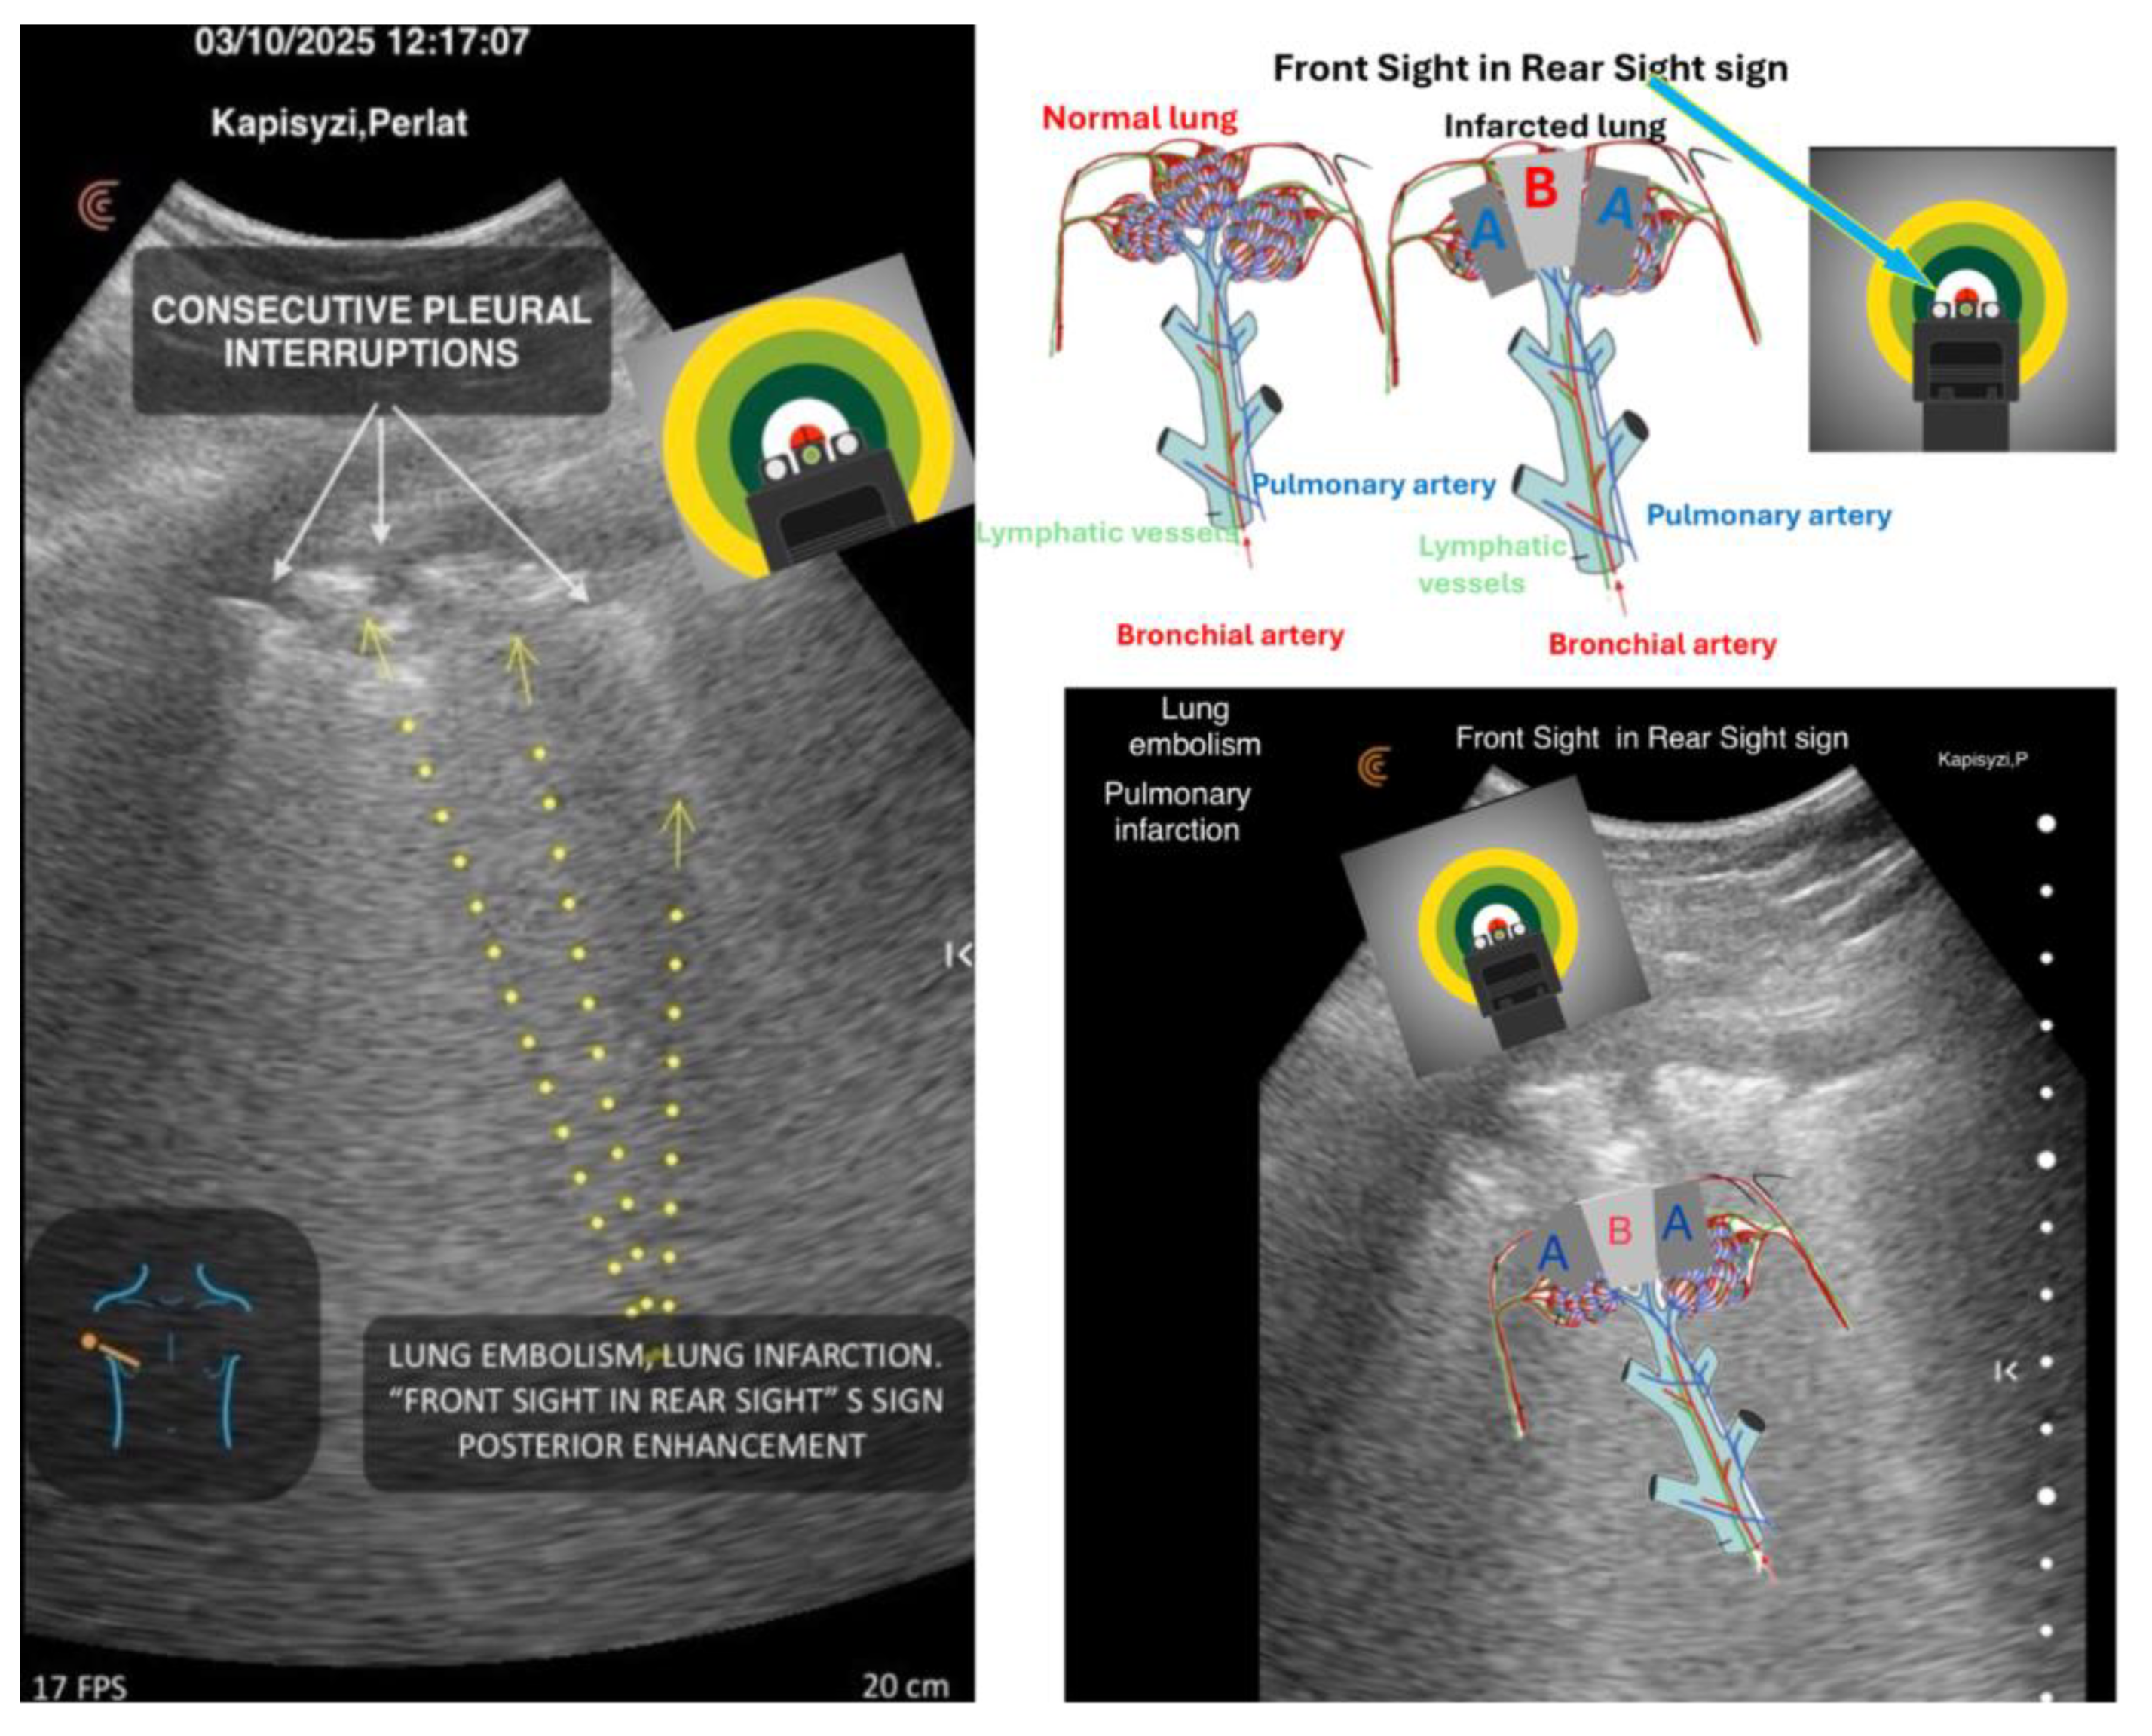

5. Front Sight in Rear Sight Sign (within Sick Bat progression)

A Geometric–Functional Hemodynamic Signature of Pulmonary Infarction

The Front Sight in Rear Sight Sign represents a distinct hemodynamic and geometric echo-phenotype of pulmonary infarction, appearing within the Sick Bat progression.It is defined by two symmetric hypoechoic zones (A)—corresponding to infarcted, non-perfused pulmonary segments—flanking a central preserved region (B) that remains perfused through bronchial arterial collateral flow.

This configuration creates a triphasic geometric pattern in which:

• Zone A (bilateral hypoechoic wedges) reflects abrupt interruption of pulmonary arterial perfusion.

• Zone B (central isoechoic or preserved band) represents the bronchial rescue zone, the only territory still receiving oxygenated blood through the systemic bronchial arteries.

• The interface between zones A and B produces a sharp, weapon-sight–like alignment, giving the sign its characteristic appearance.

Functionally, this sign establishes one of the clearest direct visual correspondences in lung ultrasound: echo morphology mirroring dual vascular supply (pulmonary vs. bronchial artery).

By making the dual-circulation physiology visible at the bedside, the Front Sight in Rear Sight Sign elevates pulmonary infarction from a non-specific “wedge-shaped hypoechoic area” to a structured hemodynamic signature, advancing the geometric-functional paradigm of this new framework. A hemodynamic echo-sign of pulmonary infarction, characterized by two hypoechoic zones (A) flanking a central preserved region (B) sustained by bronchial collateral perfusion. It establishes a direct visual correlation between echo morphology and dual vascular supply, contributing to functional interpretation of vascular injuries (Figure 3), [2].

Figure 3. Lung infarction: Front Sight in Rear Sight sign. Kapisyzi, P. ©.